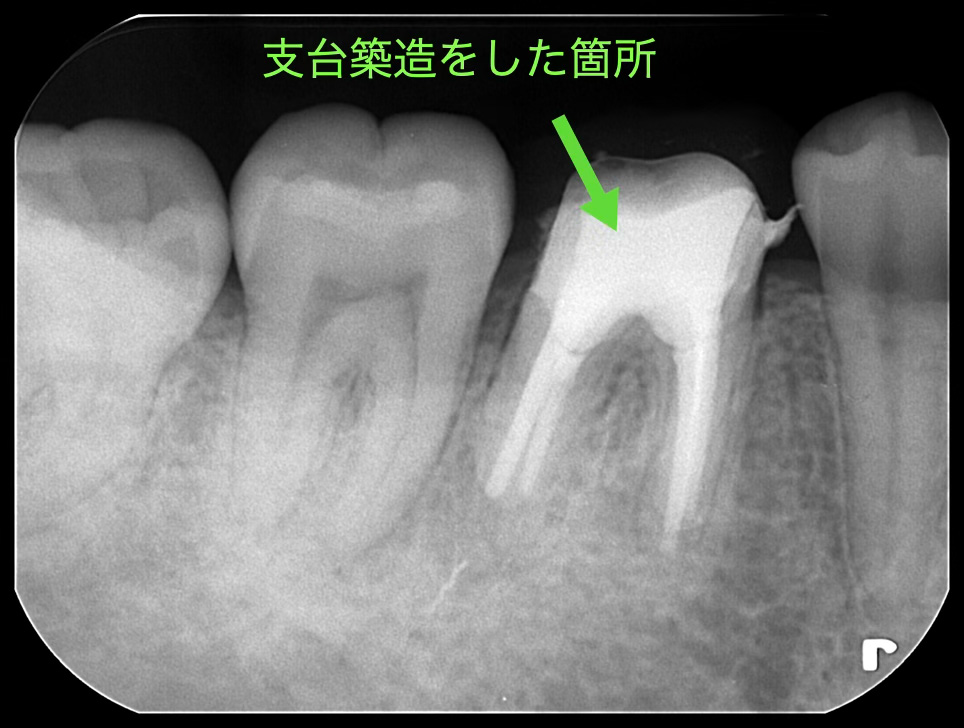

根管充填が終わった後は、歯の内側が空洞になっているため、歯の頭の部分(歯冠)の補強のために高強度の歯科用レジンを用いて、内側の空洞を歯科用レジンで満たして強度も強くします。その処置を支台築造と言います。

支台築造の後はジルコニアクラウンが被さる前に仮歯を作ります。透過像の経過を確認するために仮歯の状態で3ヶ月ほど経過を確認しました。再度レントゲンを撮影し、透過像がなくなり不透過性の亢進(レントゲンで根の先の黒い影が白く濃くなっている)のが確認がとれたため、うみがなくなり、治癒の経過が良好であったためジルコニア治療に移行しました。

だいぶ透過像がなくなっているのがわかります。骨が再生しているのがレントゲン所見からもわかります!